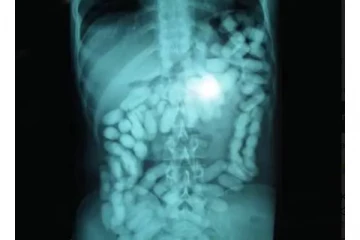

விமான நிலையத்தில் சிக்கிய நபர் - வயிற்றை சோதனை போட்ட போது அதிர்ச்சி அடைந்த அதிகாரிகள் 4 ஆண்டுகள் முன்